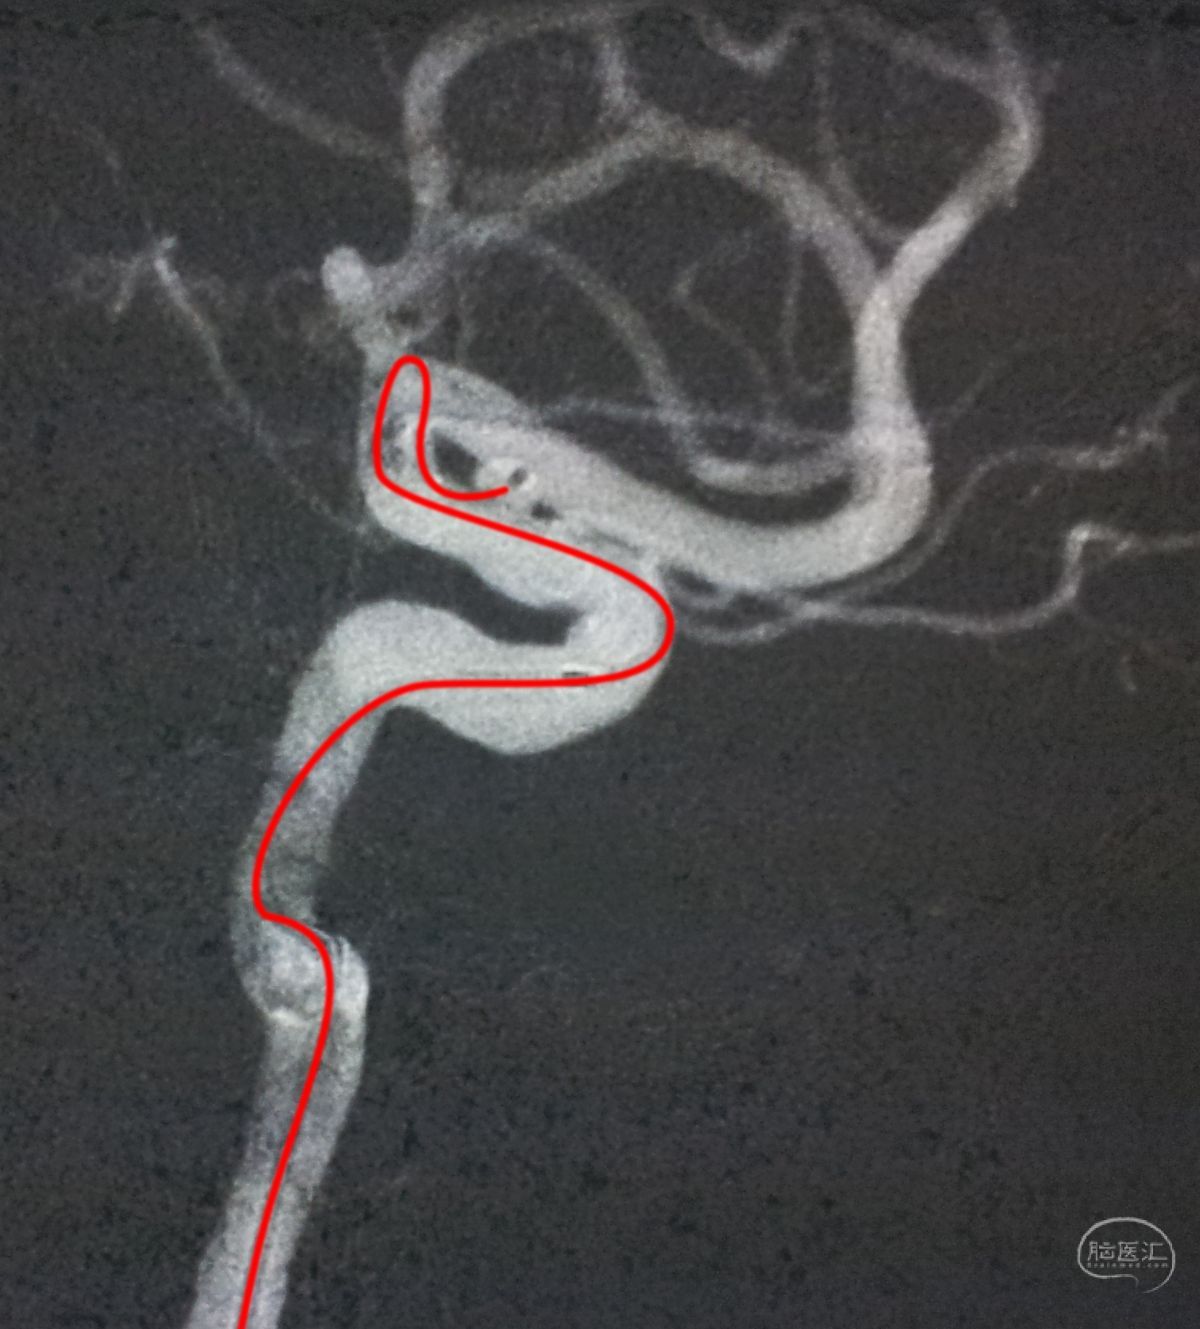

工作位造影

Traxcess 14微导丝可以进入瘤腔,但头端塑成S形的Echelon 10微导管无法跟入。

将微导管在虹吸弯处成襻,越过瘤颈,管头折返钩入瘤腔,即所谓回马枪技术。

Solitaire 4×15支架(绿线)跨瘤颈半释放,压住微导管(红线)。